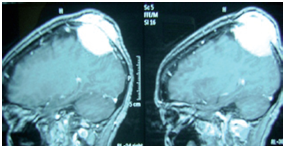

MRI demonstrated a lytic extra dural mass with contrast enhancement, eroding bone and slight cerebral tissue shift (Figure 1). Thoracoabdominal CT was normal.

Figure 1 Sagittal T1 weighted magnetic resonance image (MRI) showing the mass with invasion of the scalp (arrows).